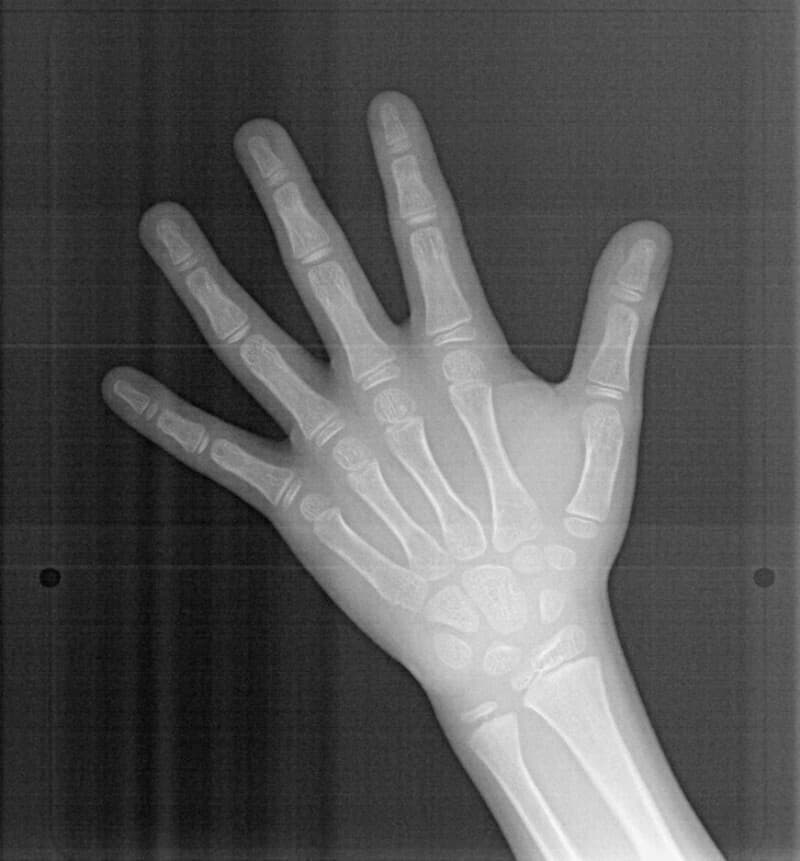

分析診断:FXフェイシャルアキシスが83度で、咬合力が極端に弱い顔面骨格ではありません。上下顎の骨格的バランスも平均値内には収まっています。Upper Molar PTV値から、上顎の奥行きが少ないとわかります。前歯の位置、E-lineと下唇の位置等から、歯が大きくて顎が小さいディスクレパンシーケースであると診断されます。

分析診断:左右の骨格的非対称が少し認められます。上顔面の幅径はさほど狭くなありませんが、下顎や下顔面の幅径は狭いと出ています。